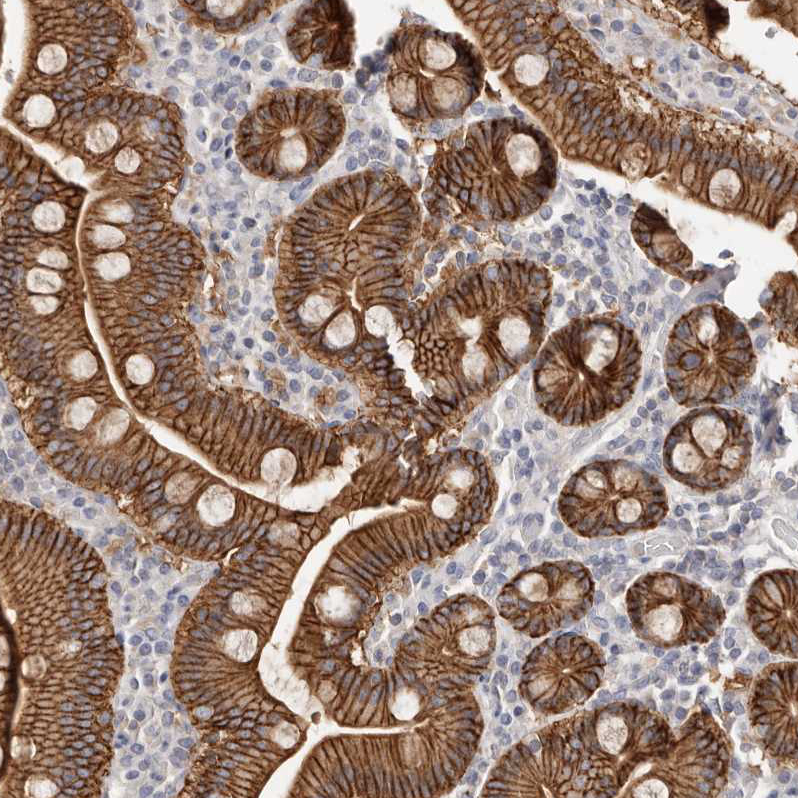

Immunohistochemistry analysis in human esophagus and liver tissues using HPA027613 antibody. Corresponding S100A14 RNA-seq data are presented for the same tissues.